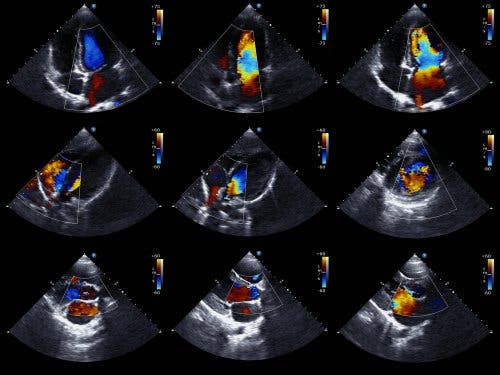

Ein Echokardiogramm ist die bevorzugte Methode zum Nachweis eines Perikardergusses. Es wird auch Echokardiographie oder Herzultraschall genannt. Dies ist eine Untersuchung, mit der Ärzte die Struktur des Herzens sehen und überprüfen können, wie gut dessen Pumpleistung ist.

Mit dem Doppler-Echokardiogramm können Ärzte auch die genaue Geschwindigkeit des Blutflusses aus dem Herzen bestimmen. Aus technischer Sicht ist das zweidimensionale und M-Mode-Echokardiogramm die ideale Technik zur Diagnose, Quantifizierung und Überwachung des Perikardergusses.

Wenn zwischen dem Epikard und dem lateralen Perikard kein Echo auftritt, können Ärzte einen Perikarderguss diagnostizieren. Dann bestimmt der Kardiologe die Größe des Ergusses basierend auf dem Abstand zwischen den beiden Schichten des Perikards.

Darüber hinaus solltest du wissen, dass es grundsätzlich zwei Arten von Echokardiogrammen gibt. Einerseits gibt es den Transthorakus, bei dem ein Gerät auf der Brust über dem Herzen platziert wird, welches Schall erzeugt. Andererseits gibt es das transösophageale Echokardiogramm, bei dem das Gerät bis zur Speiseröhre in den Verdauungstrakt eingeführt wird. Letzteres liefert detailliertere Daten.